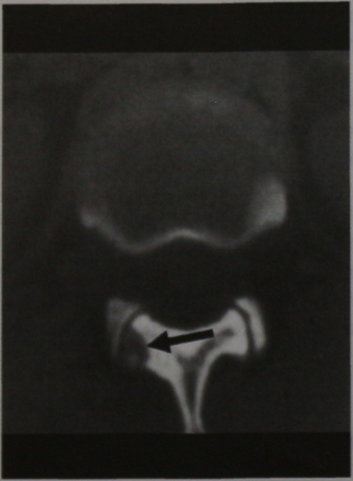

КТ (горизонтальная проекция). Подсуставной очаг с незначительным склерозом.